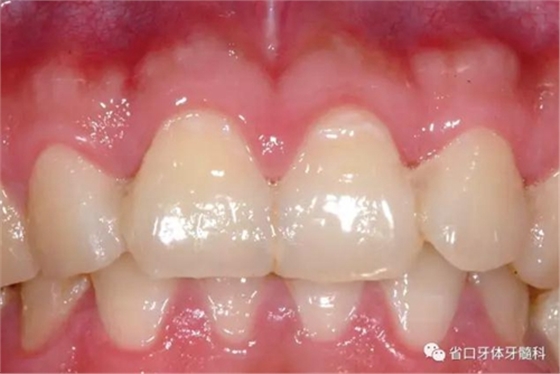

圖8:隨訪口內(nèi)照

圖9:隨訪口內(nèi)照

檢查:口腔衛(wèi)生良好,牙齦無紅腫,12-22固位良好,無松動,叩診無明顯不適,電活力測試21活力值同正常對照牙,活力值為5;

處理:建議保持口腔衛(wèi)生。定期復(fù)診行電活力測試,監(jiān)測牙髓活力。